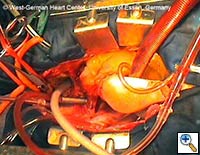

|

|

|

| Figures 4–6. These figures demonstrate advancement of the prosthesis over a transfemorally placed guide wire, the most secure method to assure appropriate placement. | ||

- The E®-vita prosthesis is then inserted into the descending aorta, with or without the accompanying guidewire. In particularly difficult descending aortic anatomy, a guidewire may be passed transfemorally, preferably via a previously inserted sheath. In some centers, the guide wire is a mandatory adjunct to secure the graft into the true lumen for aortic dissection and to avoid thrombus mobilization for aneurysms. (see Figs. 4-6 for placement over guide wire)

- The E®-vita prosthesis has 3 settings: P (Park), D (Drive), and N (Neutral). When initially unpacked, it is in Park mode. Following insertion into the descending aorta and stabilization, the mode is switched to Drive. The lever at the handle is then squeezed together repeatedly, which results in deployment of the stent. The surgeon must ensure that he keeps the position of his left hand, which is holding the lever portion of the deployment device, absolutely stable and does not pull the device back during stent deployment. Self-expansion of the stent is achieved by the nitinol wire skeleton.

- The delivery system may then be passed off, and the prosthetic graft should be pulled only a few centimeters out of the stent-graft portion of the E®-vita prosthesis. The prosthetic graft is then sewn to the proximal descending aorta using a continuous polypropylene suture (preferably 3-0 Prolene with a “Visiblack” needle). This suture line should be performed 1 - 5 cm proximal to the stent-graft / prosthetic graft junction. (see Fig. 7)